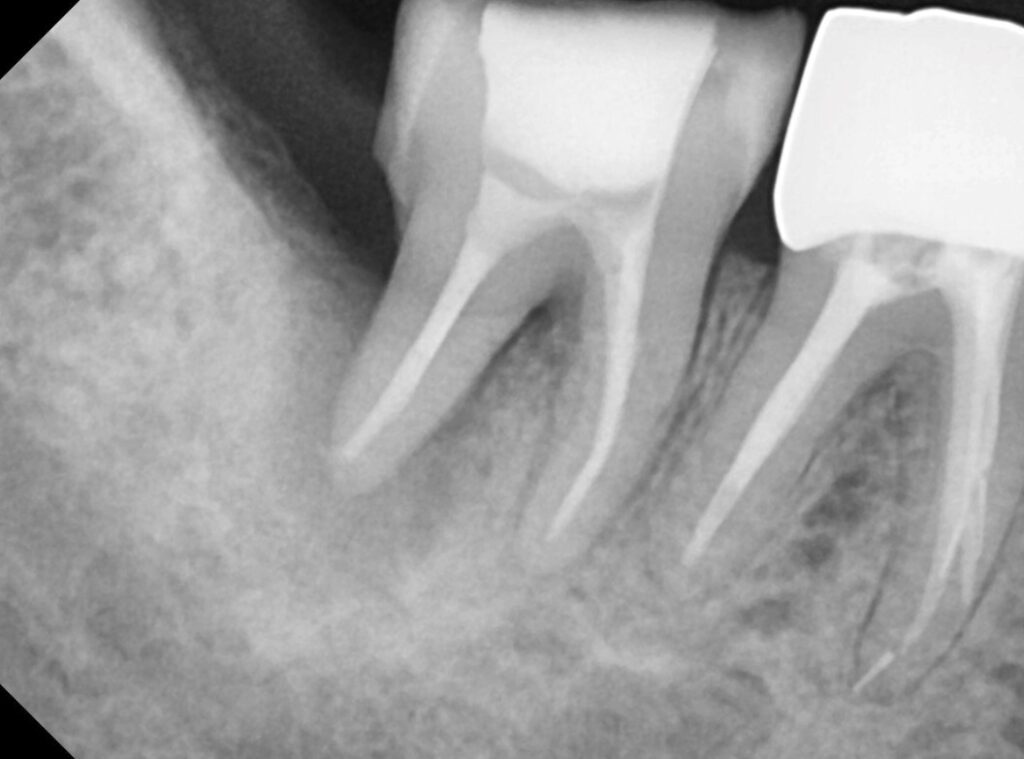

맨 좌측에 있는 큰 어금니 뺨쪽으로 고름주머니가 보입니다.

이렇게 치아 뿌리쪽으로 염증이 생겨있기 때문에 고름주머니가 생긴 것입니다.

치아 뿌리쪽으로 있던 염증이 점점 사라지고 뼈로 치유되고 있습니다.